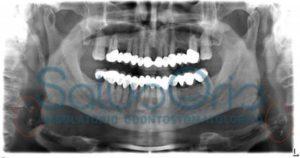

Un caso emblematico è quello del paziente a cui appartiente la radiografia panoramica mostrata sopra.

Il paziente arrivato da noi per problematiche legate alla sua vecchia protesi fissa, dopo aver eseguito una ortopantomografia, è stato informato dal nostro esperto in patologia e medicina orale che da tale radiografia erano evidenti, da entrambi i lati, delle calcificazioni del collo in corrispondenza della forcazione carotidea che con ogni probabilità erano determinate dalla presenza di placche ateromasiche alle carotidi. Il paziente non era a conoscenza delle stesse e fino a quel momento non aveva avuto sintomi specifici. Gli veniva consigliato di eseguire un Eco-color doppler dei tronchi sovra-aortici da cui veniva confermata la presenza delle suddette placche alle carotidi ed una stenosi emodinamicamente significativa di tali arterie. In altre parole, tali placche avevano creato un’ostruzione che ostacolava in maniera importante il passaggio del sangue verso il cervello; questa, in generale, è una situazione estremamente pericolosa perchè può portare ad un ictus cerebrale con conseguenze molto pericolose per la vita. Il nostro paziente, naturalmente, è stato inviato agli specialisti competenti che hanno proceduto a mettere in atto le terapie necessarie, prevenendo, così, pessime complicazioni. Competenza e preparazione, accuratezza e completezza nella diagnosi, non solo per i denti, valgono quanto la propria salute!